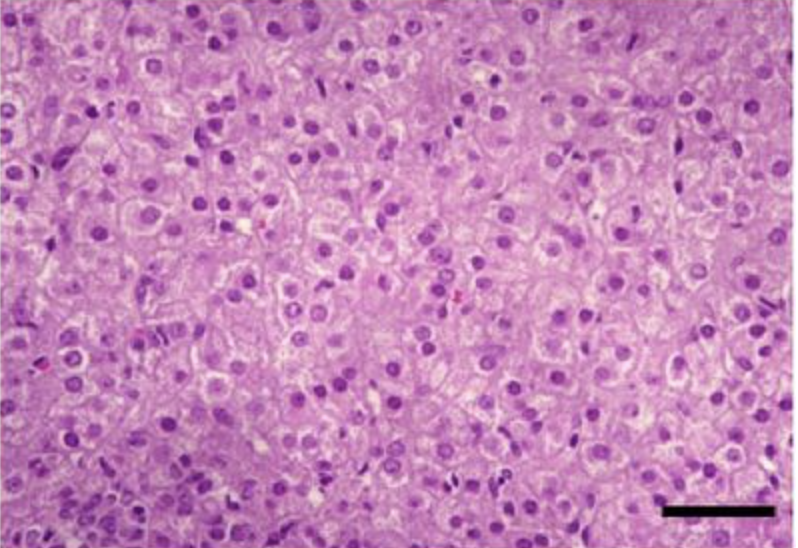

What type of gland is depicted here?

Endocrine